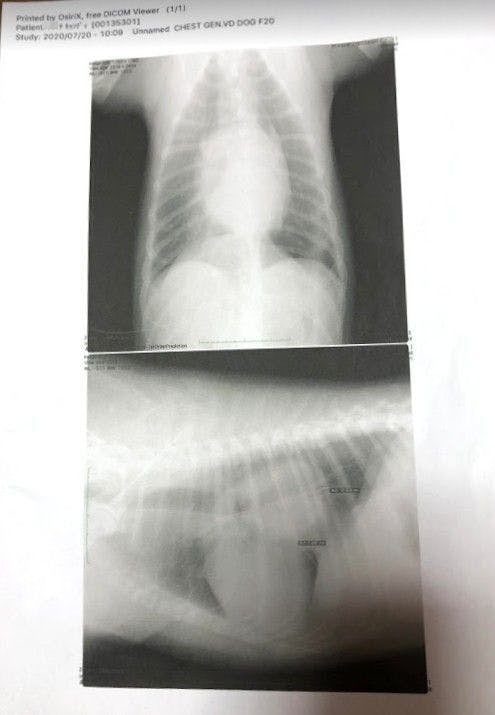

昨年末とこの7月に掛かりつけの獣医さんの所で血液検査とレントゲン検査を受けています。

元々元気な子だったので、血液検査はほとんど問題なかったのですが、レントゲン検査の結果がかなり悪くなっております。。。

腫瘍が、7か月前に比べて2倍以上大きくなっていました。(泣)

しかし大学病院で検査するには、前の検査(年末の検査)から半年も経っていたため、再度血液検査とレントゲン検査をしてみたところ、とてもショックな結果が出ました。。。(2020年7月)

これだけだとよくわからないと思うので、昨年末に撮ったレントゲン写真と並べてみました。

腫瘍の大きさが2倍以上になっていたのです(泣)

「腫瘍が心臓を圧迫していて左の肺を押しつぶしている為(右肺のみの呼吸)、通常の半分の呼吸しか出来ていず、少し歩くだけでもすぐに苦しくなる状態です。」